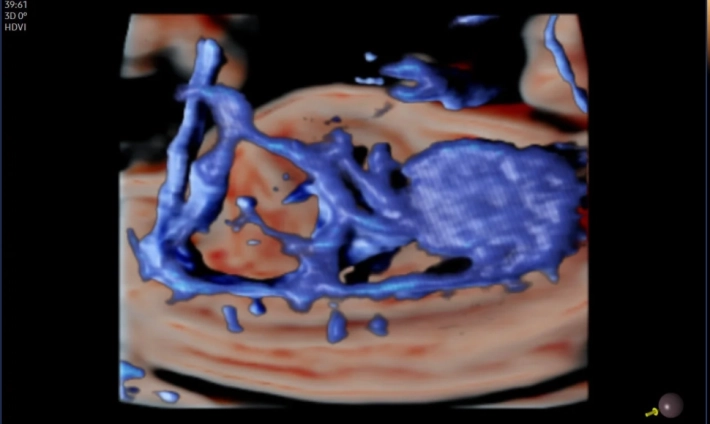

Безупречная картинка в 3D и 4D

Совершенно новый уровень визуализации плода с потрясающим качеством. Samsung Z20 открывает широкие возможности для диагностики и позволяет врачам работать максимально эффективно.

• Расширенные режимы 2D, 3D и 4D для акушерства и гинекологии;